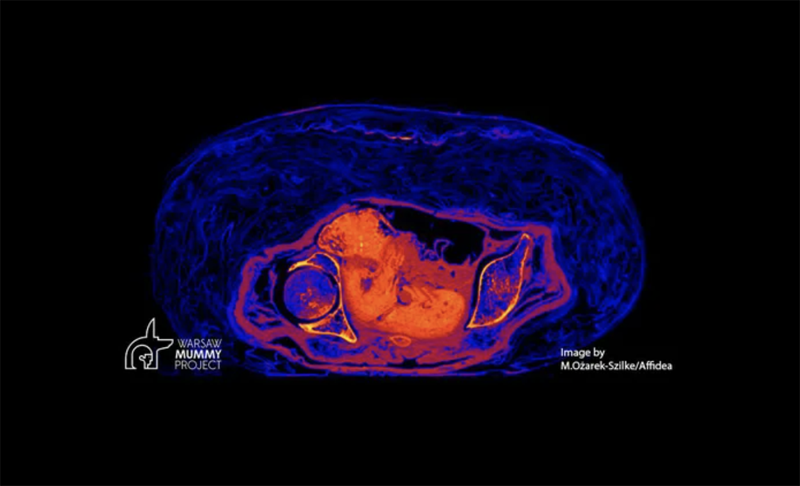

▼這具木乃伊死時的年齡在20到30歲之間,已經懷孕26到30週。更奇妙的是,木乃伊體內的胎兒在2000年後的現在,仍能保持完整。

▼研究團隊表示,木乃伊的製作方式,導致子宮成為了低氧環境,隨著遺體的血液pH值下降,再加上子宮內容物的分解,內部的酸性愈來愈高。研究團隊比喻說,胎兒就像被「醃製」一般。

▼木乃伊體內的胎兒外表保存良好,但骨頭幾乎完全消失了。科學家認為,這也是子宮內的高酸性環境導致的,胎兒的骨骼才會出現「脫礦」現象。胎兒在木乃伊的子宮內,就像將遺體放入沼澤中保存一般。